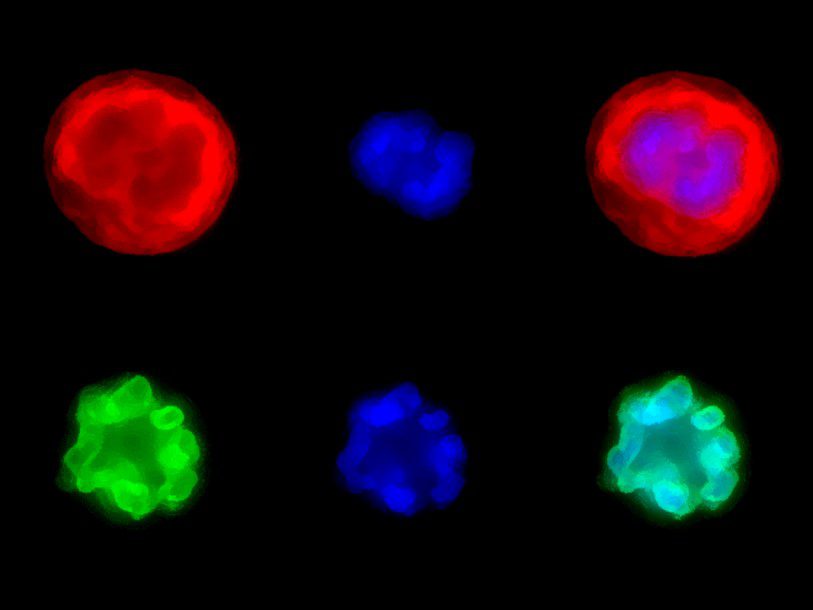

Research at the Pfizer-University of Granada-Junta de Andalucía Centre for Genomics and Oncology Research (GENYO) is organised into two main areas: Functional Genomics, which corresponds to the basic area, and Personalised Medicine, focused on clinical applications. These areas are structured into strategic lines. The Functional Genomics area focuses on the study of the human genome and cancer genomics, addressing the fundamental mechanisms of genetic and molecular biology. The area of Personalised Medicine focuses on the detection, diagnosis, monitoring and prognosis of diseases, as well as the design and implementation of advanced therapies, with the aim of translating scientific knowledge into personalised solutions for patients. This structure allows GENyO to integrate basic and applied research, driving significant advances in the field of genomics and oncology.